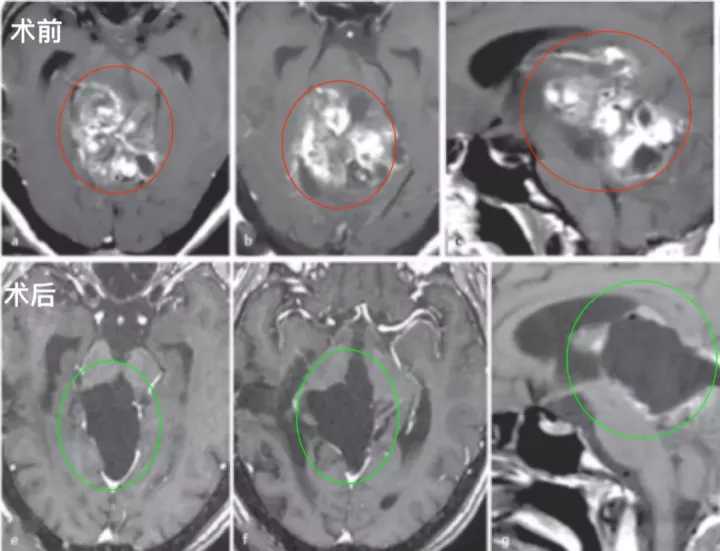

术前:28岁女性,有进行性步态共济失调和轻微复视。在德国INI就诊的四年前,在本国医院被诊断出中脑顶盖肿瘤,接受了两次外科手术,活检诊断为毛细胞星形细胞瘤。随着肿瘤继续长大,建议患者在其他地方接受放疗,然后用替莫唑胺进行化疗,为期12个月,然而治疗均未达到有效的肿瘤控制。随后联系德国巴特朗菲教授进行会诊,得到了教授可以为其治疗的全切手术方案,遂转诊到德国治疗。

术后:术后第1天,ICU治疗观察。术后第2天:复查CT正常,拔除气管插管,有轻微头痛,可完全自主呼吸。术后第4天:患者无明显呼吸机活动障碍,复视有所好转,无肢体瘫痪、面瘫等,转至普通病房继续治疗。患者能在协助时下床、简单日常活动,在康复师指导下进行康复锻炼,头痛明显好转,步态不稳好转,肢体无力稍好转,无呼吸抑制、肢体瘫痪加重等手术相关并发症。术后第10天:顺利拆线,术后3周出院,无头痛、肢体无力等,复视、步态不稳较术前明显好转。

术后影像复查:轴位(e,f)和矢状位(g)T1加权增强MRI检查显示,外生型毛细胞星形细胞瘤被成功切除。病人没有出现手术相关的神经功能损伤,随后的随访病程平安无事。

图:术前术后脑磁共振对比,巨大脑干胶质瘤全切,无神经脑组织损伤。